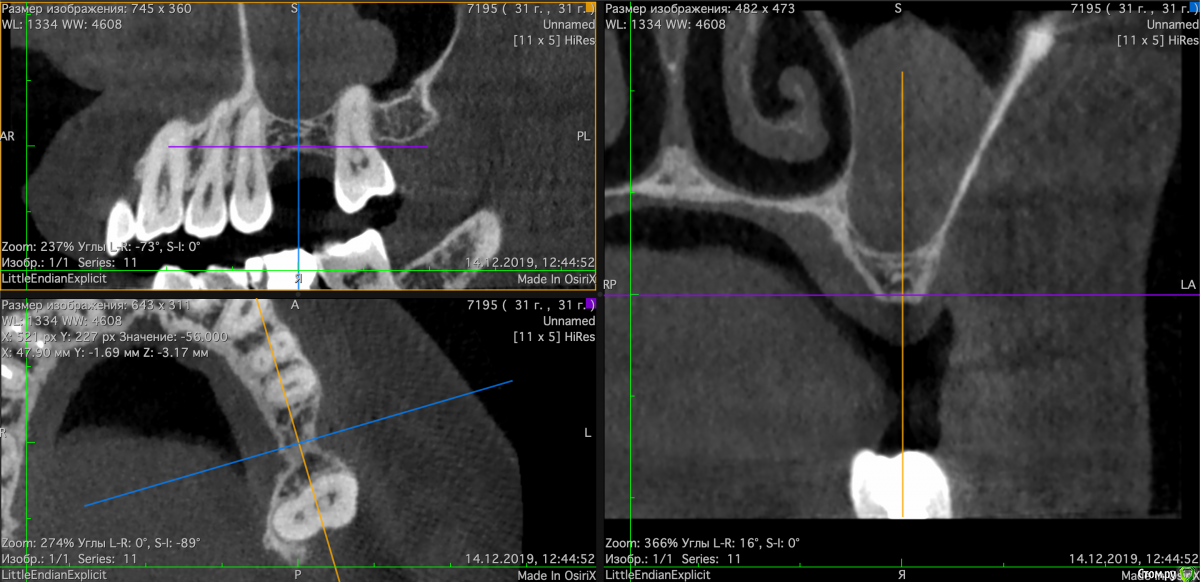

Valerkaa Опубликовано 14 декабря, 2019 Автор Поделиться Опубликовано 14 декабря, 2019 ну и кейс №2, чтобы не плодить темы. Пациентка планирует имплантацию в области 1.6, на КТ вот такая штука в пазухе. Нужен синус, отправила лечиться к Лорам. Это КТ на сегодня, т.е после лоров, около 4 месяцев назад была примерно такая же картина. Что делать, пусть ищет хорошего Лора? Жалоб со стороны пазухи нет. Ссылка на комментарий

Kev Опубликовано 15 декабря, 2019 Поделиться Опубликовано 15 декабря, 2019 Нужны все размеры, в частности до канала (кейс №1) и до пазухи (кейс №2). Ссылка на комментарий

Valerkaa Опубликовано 15 декабря, 2019 Автор Поделиться Опубликовано 15 декабря, 2019 Большое спасибо. Вот с размерами. №1 и №2 Ссылка на комментарий

Bier Опубликовано 30 декабря, 2019 Поделиться Опубликовано 30 декабря, 2019 Кейс номер 1Устанавливать с заглублением конический или TL имплантат. Без пластики, без "чистки" кости. Кейс номер2Ретенционная киста, ЛОР лечения не требует. Можно сдуть ее шприцем или удалить на операции. 2 Ссылка на комментарий